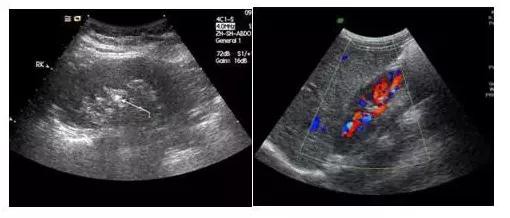

眾所周知,B超檢查是體驗中必不可少的項目,它可直觀而清晰地發現人體各臟器如肝、腎、胰腺、甲狀腺、乳腺、膀胱等的多種病變。B超又有黑白超和彩超之分,有時我們做黑白B超檢查,有時是彩色B超。其實對患者來說除了兩者價格有高低外,對它們之間的差別并不十分清楚。是越貴越…